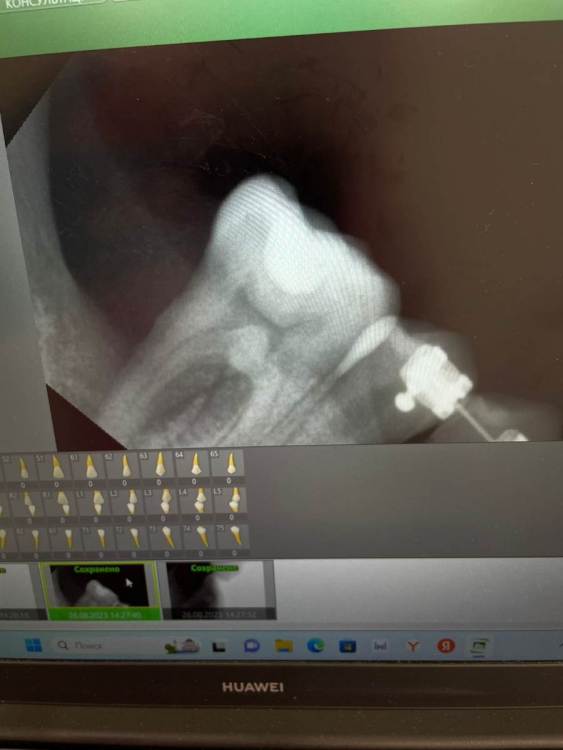

Graf Опубликовано 26 августа, 2023 Поделиться Опубликовано 26 августа, 2023 Пациентка пришла с жалобами на пульсирующие боли и небольшую опухлость в области 46 зуба. Что можете сказать по данному случаю и есть ли возможность сохранить этот зуб? Ссылка на комментарий